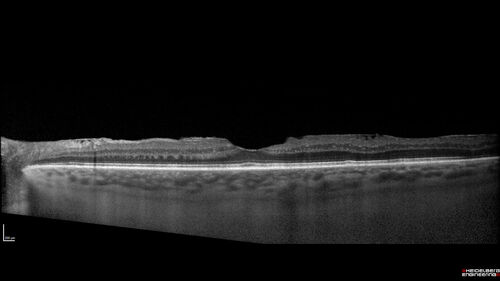

Serous Macular Detachment from Small Choroidal Melanoma

72 year old female misdiagnosed as CSR who had small choroidal melanoms.